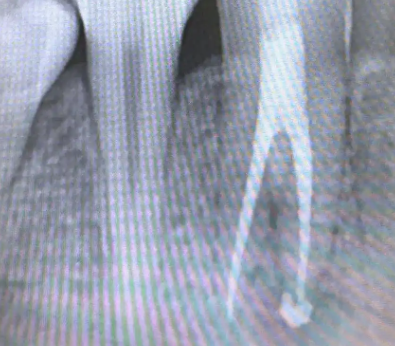

1. 根管治疗(首选方案)

清除坏死牙髓和细菌;

彻底消毒并严密充填根管;

多数患者经规范根管治疗后可保留患牙,避免拔牙。